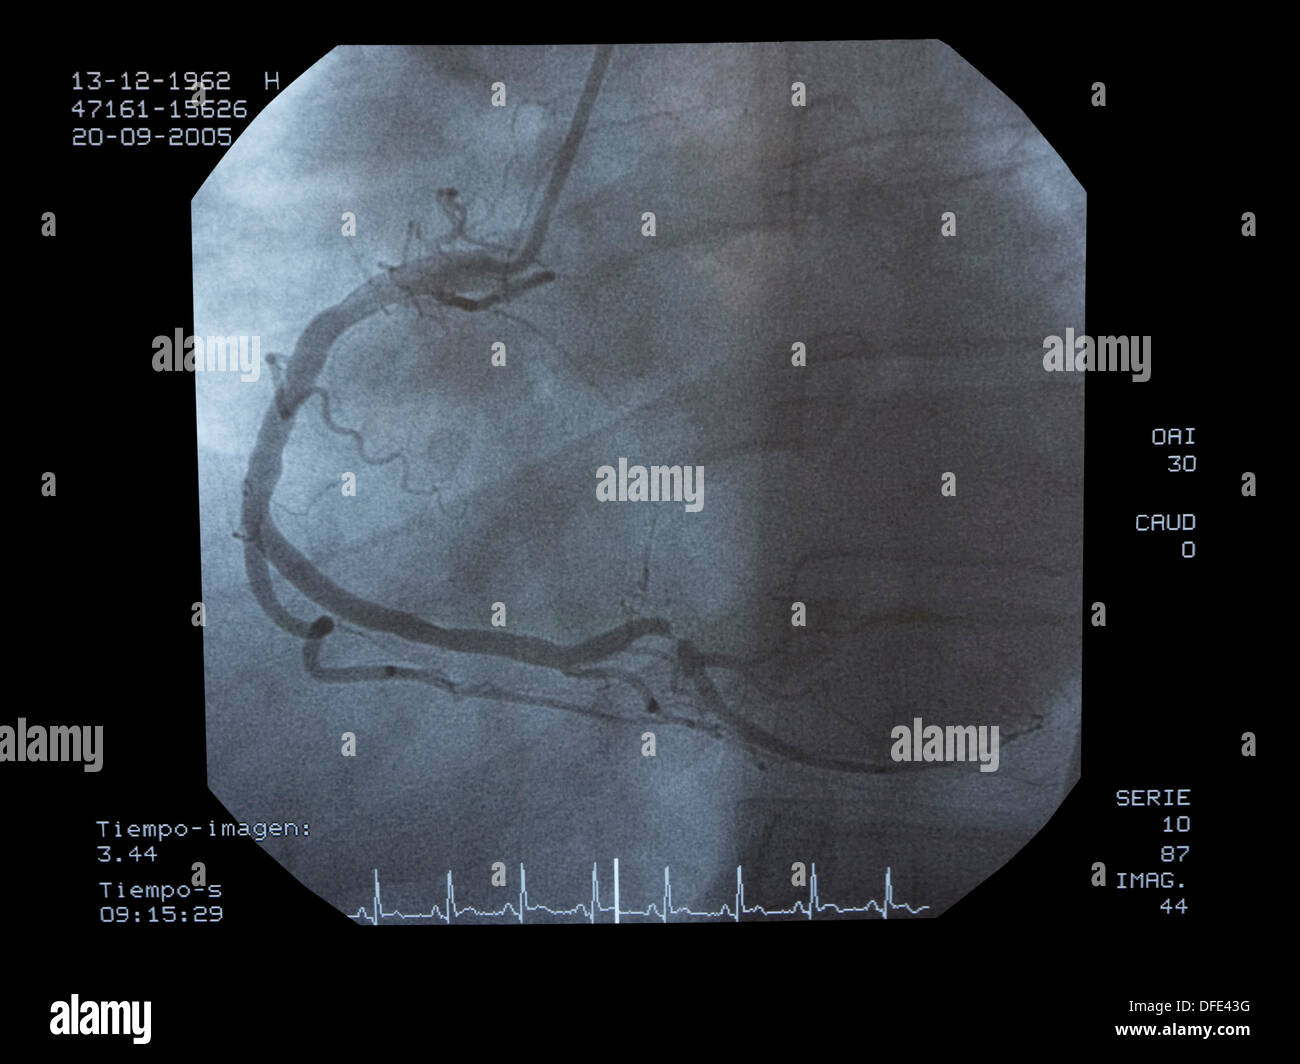

From www.alamy.com

Angiography, implantation of ICD (Automatic Implantable Cardioverter Defibrillator Radiology Implantable cardioverter defibrillator (icd) is an electronic device with a defibrillator unit capable of generating and. There are two types of cardiac conduction devices (ccd's): Cardiac pacemaker and implantable cardioverter defibrillator (icd) systems are commonly seen on chest radiographs. In 2009, more than 300,000 adults and children in the united states underwent placement of a new pacemaker or icd, and. Defibrillator Radiology.